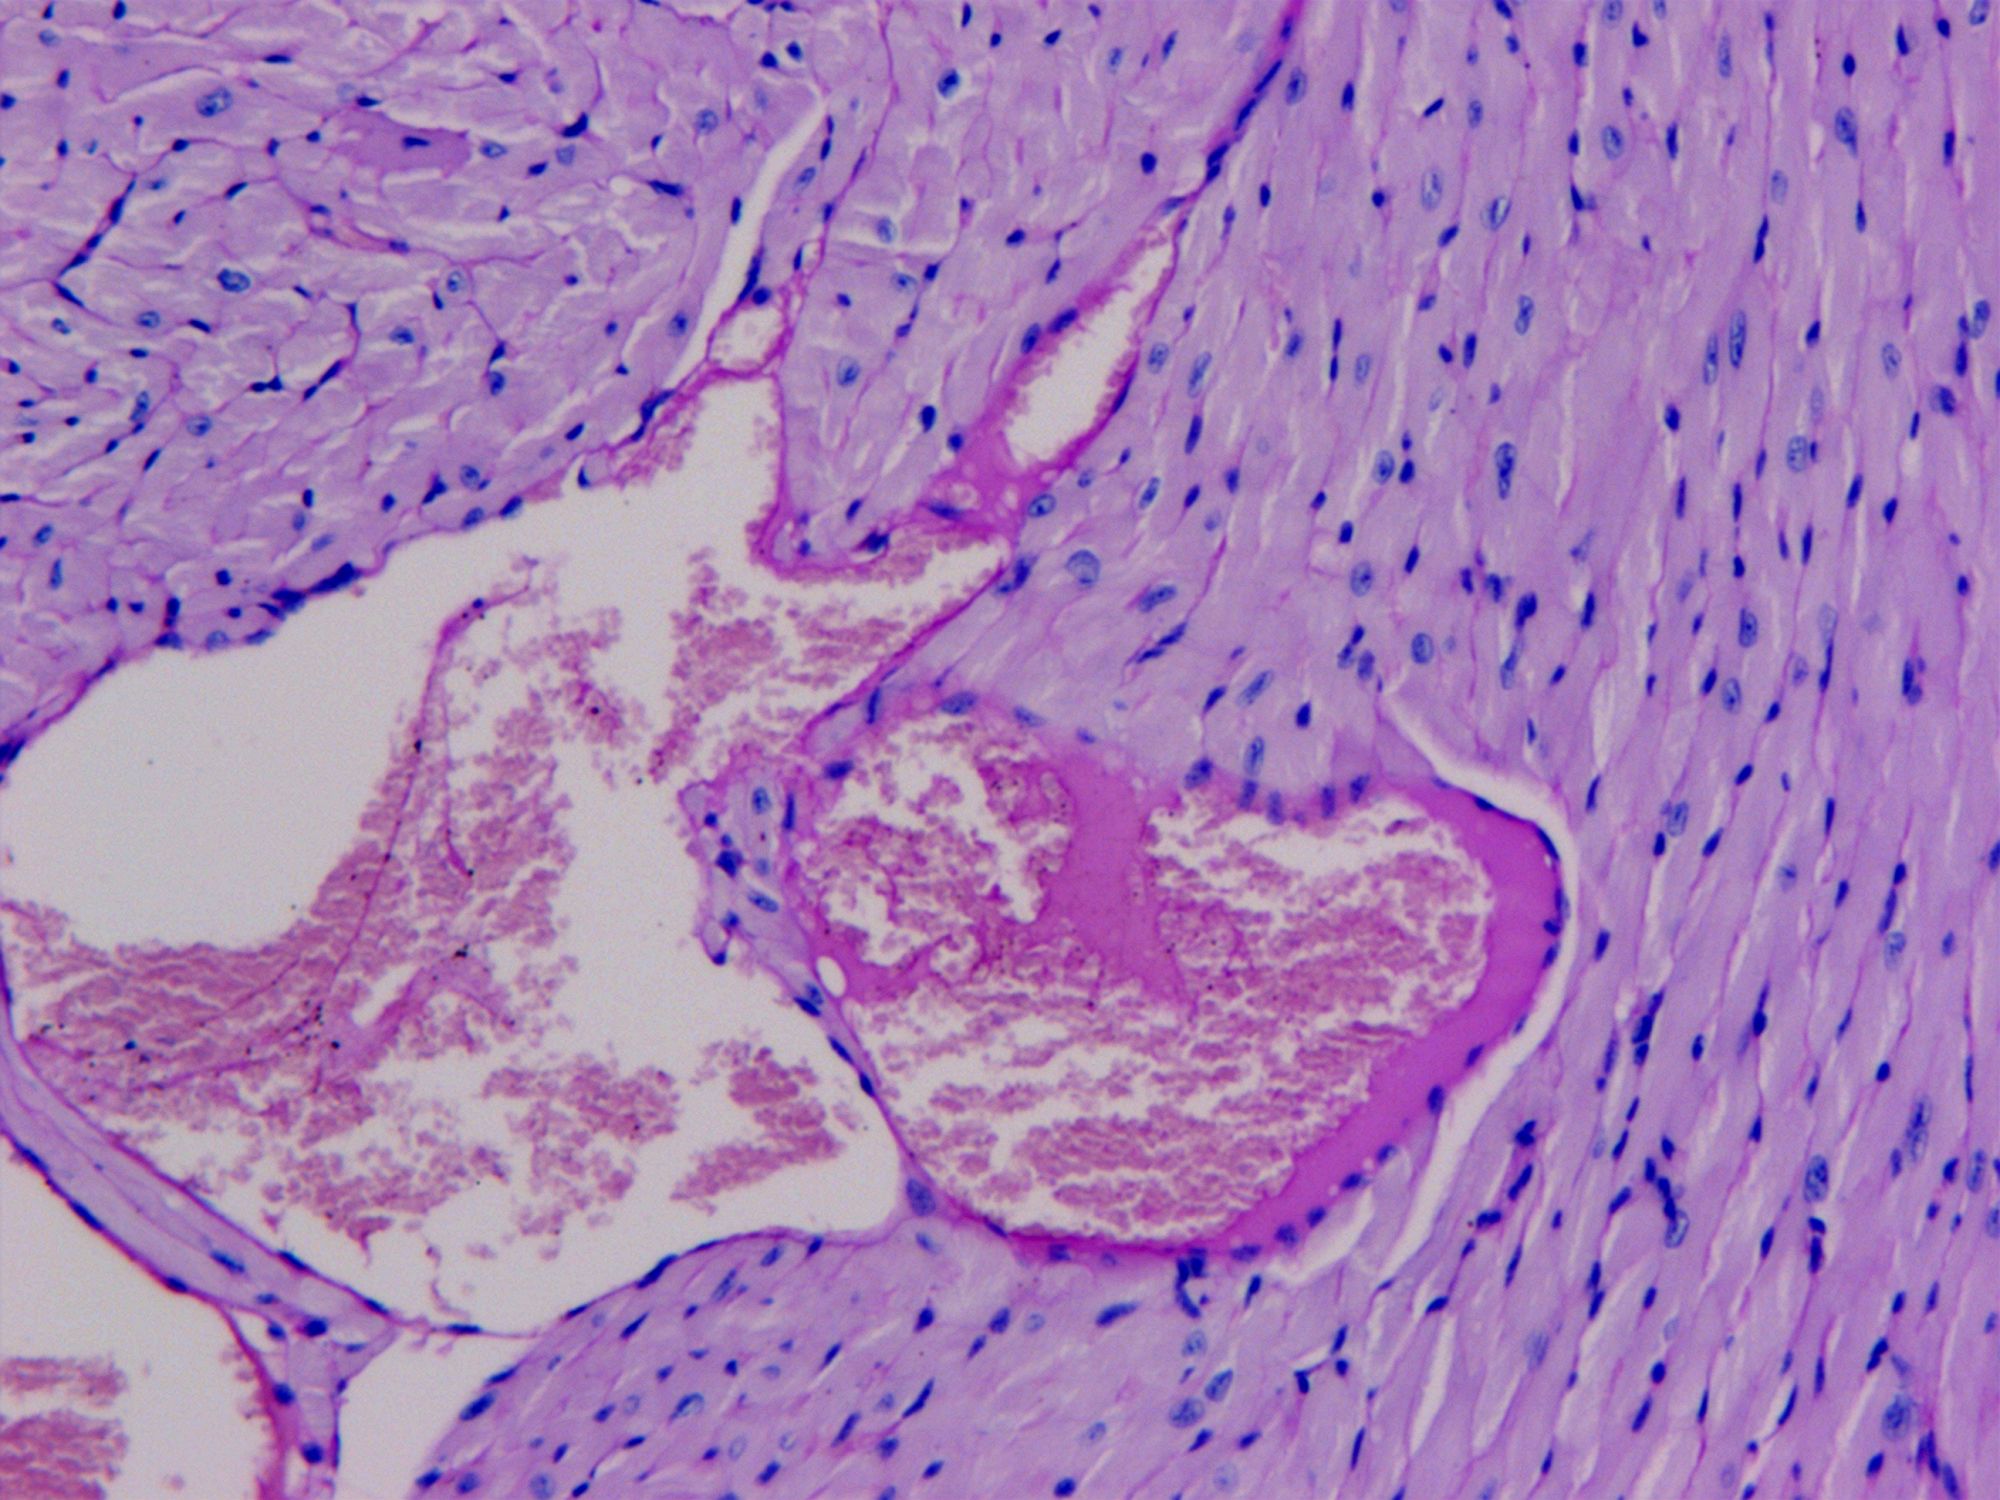

PAS染色法(Periodic Acid-Schiff stain)在組織學(xué)上,又稱過(guò)碘酸雪夫染色,糖原染色。一般用來(lái)顯示糖元和其它多糖物質(zhì),過(guò)碘酸把糖類相鄰兩個(gè)碳上的羥基氧化成醛基,再用Schiff試劑和醛基反應(yīng)使呈現(xiàn)紫紅色。

PAS染色糖原染色是病理學(xué)中常規(guī)的染色方法之一,氧化劑能氧化糖類及有關(guān)物質(zhì)中的1,2-乙二醇基,使之變?yōu)槎?,醛與Schiff試劑能結(jié)合成一種品紅化合物,產(chǎn)生紫紅色。PAS技術(shù)常用來(lái)顯示糖原和其他多糖,該染色液不僅能夠顯示糖原,還能顯示中性黏液性物質(zhì)和某些酸性物質(zhì),以及軟骨、垂體、霉菌、真菌、色素、淀粉樣物質(zhì)、基底膜等。

PAS反應(yīng)陽(yáng)性物質(zhì) 紅色或紫紅色

細(xì)胞核 藍(lán)色

細(xì)胞質(zhì) 深淺不一的紅色